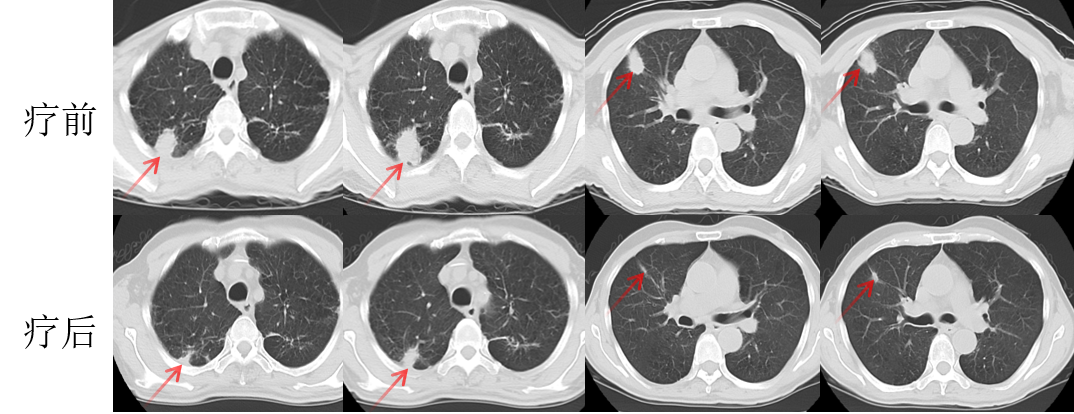

林老先生,67歲,患者2024年8月因咳嗽、咳痰,并發(fā)現(xiàn)頸部包塊入院。入院后經(jīng)CT檢查發(fā)現(xiàn),肺內(nèi)及頸部可見多發(fā)腫瘤病灶(見圖)。于2024年8月21日行超聲引導(dǎo)下頸部淋巴結(jié)穿刺活檢術(shù)。術(shù)后病理提示:右頸轉(zhuǎn)移性肺腺癌。頭部磁共振檢查顯示,顱內(nèi)多發(fā)腦轉(zhuǎn)移瘤病灶(見圖)。診斷為肺腺癌,腦、頸部淋巴結(jié)、肺內(nèi)多發(fā)轉(zhuǎn)移IVB期。進(jìn)一步對(duì)患者腫瘤組織進(jìn)行腫瘤組織基因檢測(cè)和免疫檢查點(diǎn)分子——細(xì)胞程序性死亡配體1(PDL1)檢測(cè)。

圖注:CT檢查,肺內(nèi)及頸部可見多發(fā)腫瘤病灶。

患者基因檢測(cè)結(jié)果為陰性,沒有找到具有靶向治療藥物的突變基因。此外,患者年齡較大,體質(zhì)非常瘦弱,全身多發(fā)轉(zhuǎn)移病灶,為治療帶來了巨大的挑戰(zhàn)。然而,患者PDL1檢測(cè)顯示,PDL1高表達(dá)(PD-L1患者TPS98% CPS100%),提示免疫治療有效率較高。潘振宇教授團(tuán)隊(duì)為患者制定了個(gè)體化精準(zhǔn)腫瘤治療方案,患者于2024年9月21日開始接受頭部放療。采用最新一代智慧化精準(zhǔn)放療系統(tǒng)——Halcyon“速銳刀”,成功控制患者全部顱內(nèi)病灶。治療過程順利,沒有副反應(yīng)發(fā)生。隨后,給予患者每3周1次免疫治療。經(jīng)過3次免疫治療后復(fù)查,患者肺內(nèi)病灶顯著縮退,癥狀明顯恢復(fù),沒有明顯副反應(yīng)發(fā)生。目前狀態(tài)恢復(fù)良好,生活完全自理。

圖注:治療后復(fù)查胸部CT顯示,肺內(nèi)病灶明顯縮小,頸部淋巴結(jié)轉(zhuǎn)移病灶基本消失。